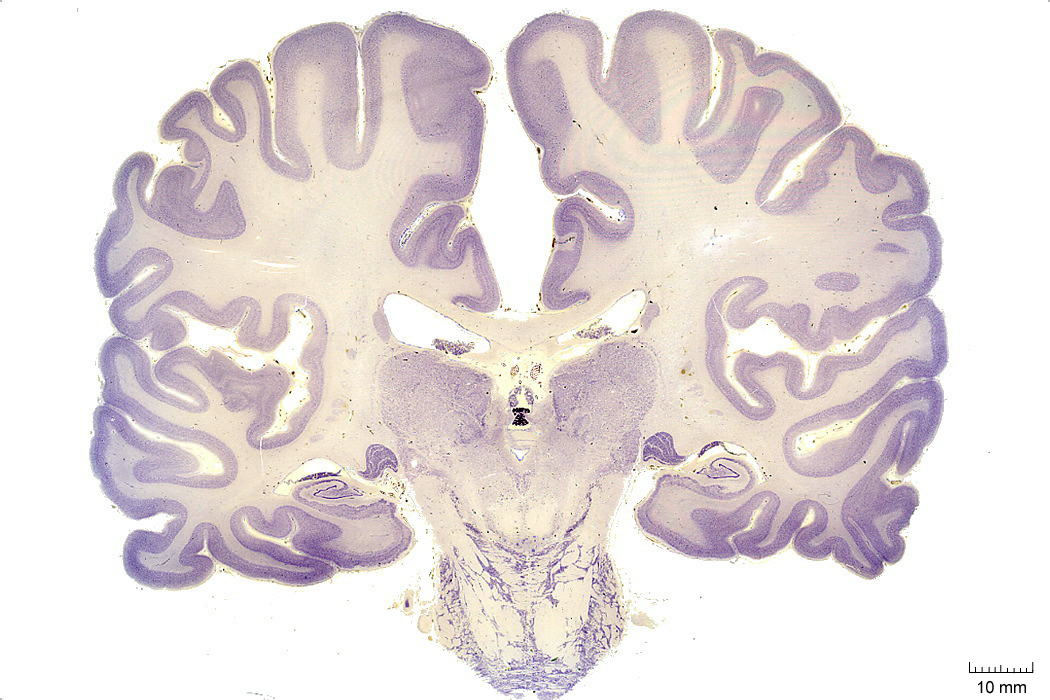

Common techniques to visualize brain structure

Note:

- Cell stain is Nissl stain

- Fiber stain is Luxol Fast blue

- Nissl stain

- basic dyes (e.g. aniline, thionine, or cresyl violet)

- stain negatively charged RNA blue

Cell groupings: cortex vs nuclei

Here is one of those cell body violet stained sections-- you can see the cortical sheet and different subcortical nuclei in the thalamus, etc. We will go over this in more detail later.